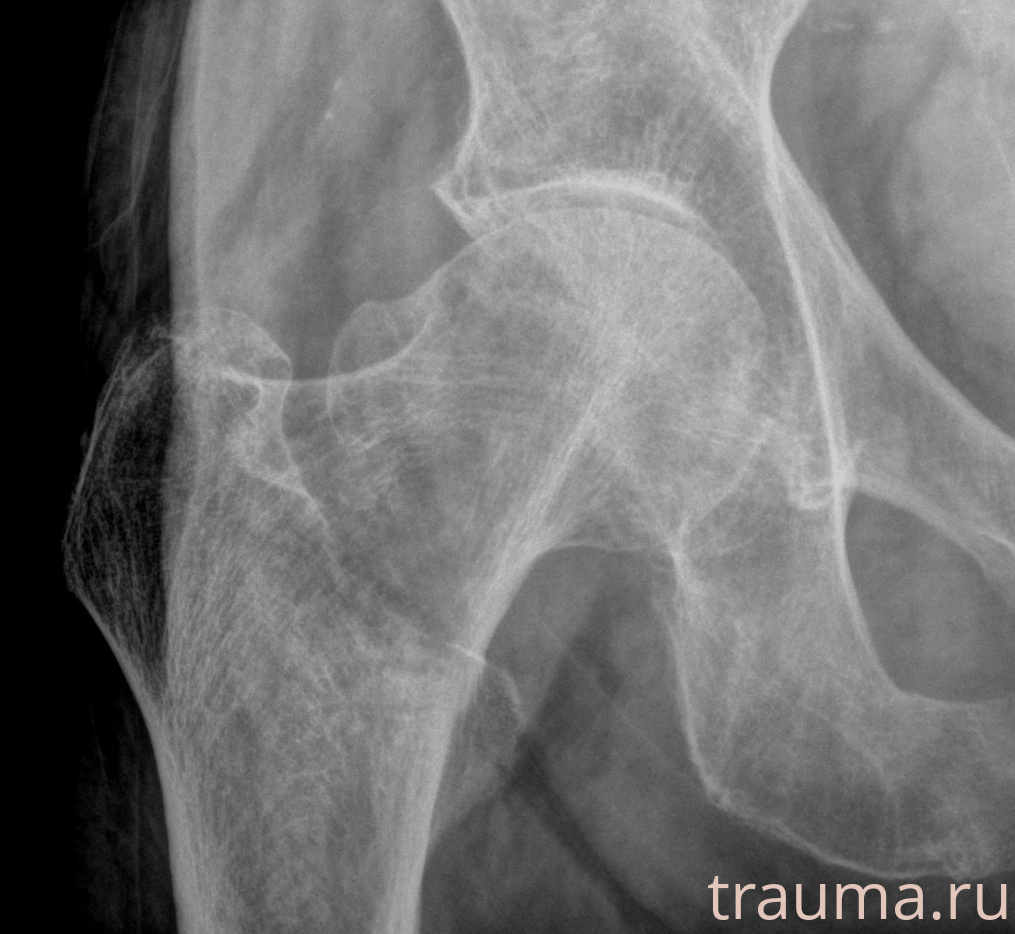

Рентген на дому: по вашему адресу приезжает врач-рентгенолог, травматолог-ортопед с мобильным рентгеновским аппаратом, проводит диагностику травмы или заболевания, делает необходимые рентгенограммы, дает рекомендации по дальнейшему лечению. Получить качественные снимки в домашних условиях возможно благодаря уникальной методике, разработанной МосРентген Центром для института  Склифосовского